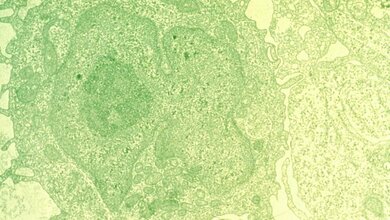

Die Strahlentherapie wird oft verwendet, um Krebs zu behandeln. Ein Nachteil der Behandlung ist, dass die Strahlung auch gesundes Gewebe schädigen kann. Es gibt bereits verschiedene komplexe Systeme und Methoden, um den Tumor mit so viel Präzision wie möglich zu erreichen, aber es gibt keine Remote-Methode im Inneren des Körpers, um zu überprüfen - in situ - ob die Strahlung ihr Ziel tatsächlich erreicht hat.

Professor Koen Van Den Abeele und seine Kollegen haben nun einen Weg gefunden, dies zu ändern. Ihre neue Technik kombiniert gasgefüllte Mikrobläschen und Schallwellen, um zu bestimmen, ob die Bestrahlung den Zielbereich erreicht hat. Die Mikrobläschen haben etwa die Größe der roten Blutkörperchen und werden in den Blutstrom injiziert. Einmal im Inneren des Körpers, binden sie an den Tumor. Die Exposition gegenüber Strahlung macht die Mikrobläschen steifer. Diese lokale Änderung der Steifigkeit ist das, was die Forscher mit Ultraschallwellen erfassen können.

Mikrobläschen werden bereits als Kontrastmittel für die Ultraschall-basierte medizinische Bildgebung von Gewebe, Organen und Blutstrom zur Arzneimittelabgabe oder für den Gentransfer verwendet. Diese neue Technik ist die erste, die Mikrobläschen für die Dosimetrie im Kampf gegen den Krebs einsetzt.